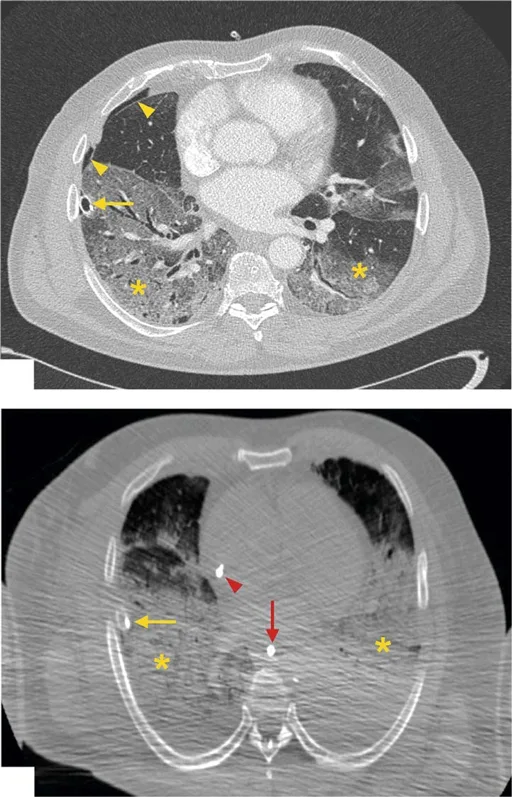

Figure 1. Imagerie par tomodensitométrie (TDM) antemortem versus post-mortem (cas 3).

Haut. La tomodensitométrie améliorée au moyen de contraste démontre les résultats antémortem: opacités bilatérales en verre dépoli dans les lobes inférieurs des deux poumons ( astérisques jaunes ) et un drain thoracique ( flèche jaune ), qui a été introduit pour traiter un pneumothorax ( pointes de flèches jaunes ). Bas. La tomodensitométrie sans amélioration du produit de contraste démontre les résultats post-mortem correspondants. Pour des raisons techniques, l’image post-mortem a une résolution inférieure. Pour protéger le personnel contre une infection potentielle, les corps ont été scannés dans un sac mortuaire à double épaisseur avec les bras positionnés le long du corps. Bien que les résultats correspondent aux images antemortem, les opacités du verre dépoli dans les deux lobes inférieurs ( astérisques jaunes) et un drain thoracique ( flèche jaune ) sont visibles. De plus, une ligne veineuse centrale ( pointe de flèche rouge ) et une sonde gastrique ( flèche rouge ) sont visibles.